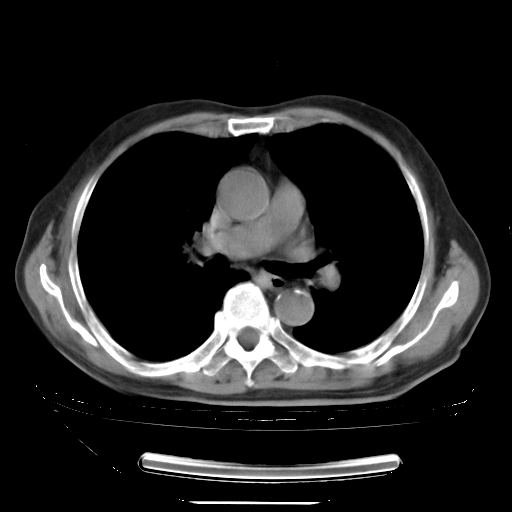

今天复查肺部CT,发现双肺广泛磨玻璃样改变。所以我把3月19日和5月9日相隔50天的肺部CT上传。请大家会诊。

2009年3月19日肺部CT片。

5月9日肺部CT(在4月27日齐鲁医院肺部CT描述部分肺组织磨玻璃样改变,12天后肺组织广泛磨玻璃样改变)